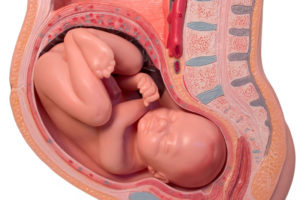

Матка является мышечным органом, состоящим из трех слоев. Снаружи она покрыта особой пленкой – параметрием, а изнутри выстлана слизистой оболочкой – эндометрием, где формируется плацента и плодные оболочки при беременности.

Мышечная ткань при беременности способна разрастаться и увеличиваться в толщине и размерах, имеет свойства сокращаться.

Как, например, это происходит при родах, чтобы помочь ребенку родиться. Но, в своем обычном состоянии миометрий должен быть расслаблен, в том числе и во время беременности – это и будет нормальным тонусом матки.

Если при беременности, до начала родов, мышцы матки сокращаются, и она уплотняется, говорят о повышении тонуса матки.